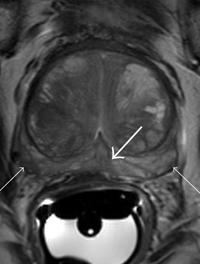

Traitement substitutif par testostérone et risques prostatiques : bonne nouvelle !

La relation entre traitement substitutif par la testostérone de l’hypogonadisme masculin et cancer de la prostate restent imprécises. Un vaste essai randomisé plaide en faveur de l’absence de majoration d’événements prostatiques sous TRT, sous réserve d’exclure les hommes à plus haut risque.